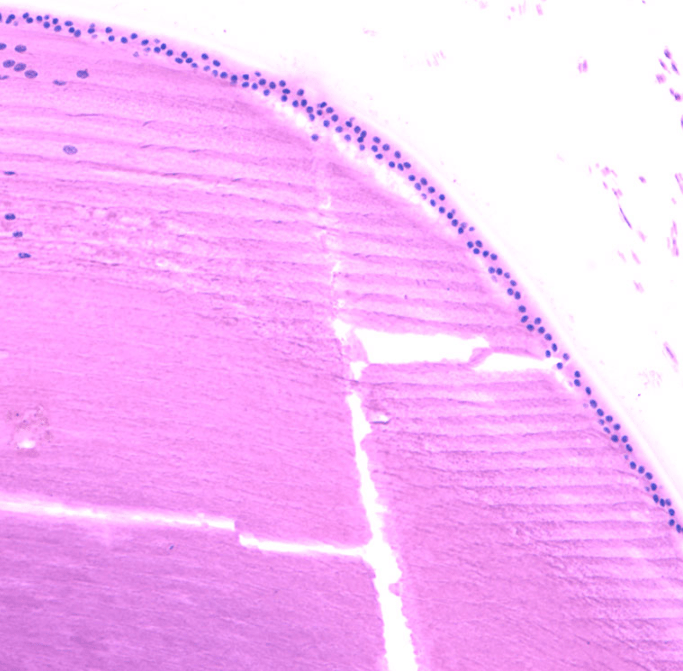

CRISTALINO